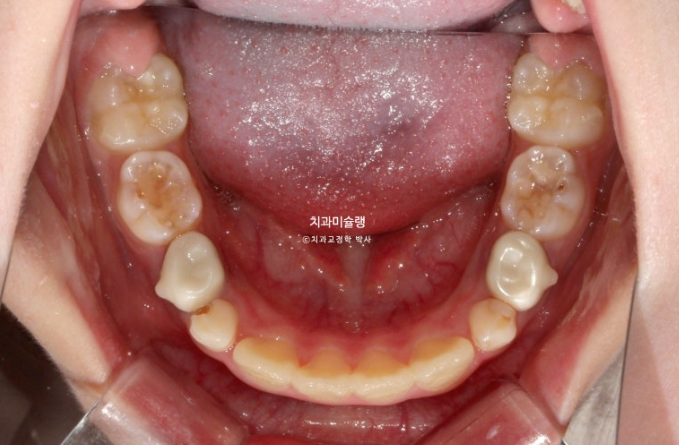

아래도 마찬가지 입니다.

앞니가 벌써 삐뚤삐뚤 합니다.

송곳니가 나올때는 어떻게 될까요?

덧니 100% 예약입니다.

어린이 교정은 악궁확장을 통해 이가 날 공간을 넓히는 과정이 동반이됩니다.